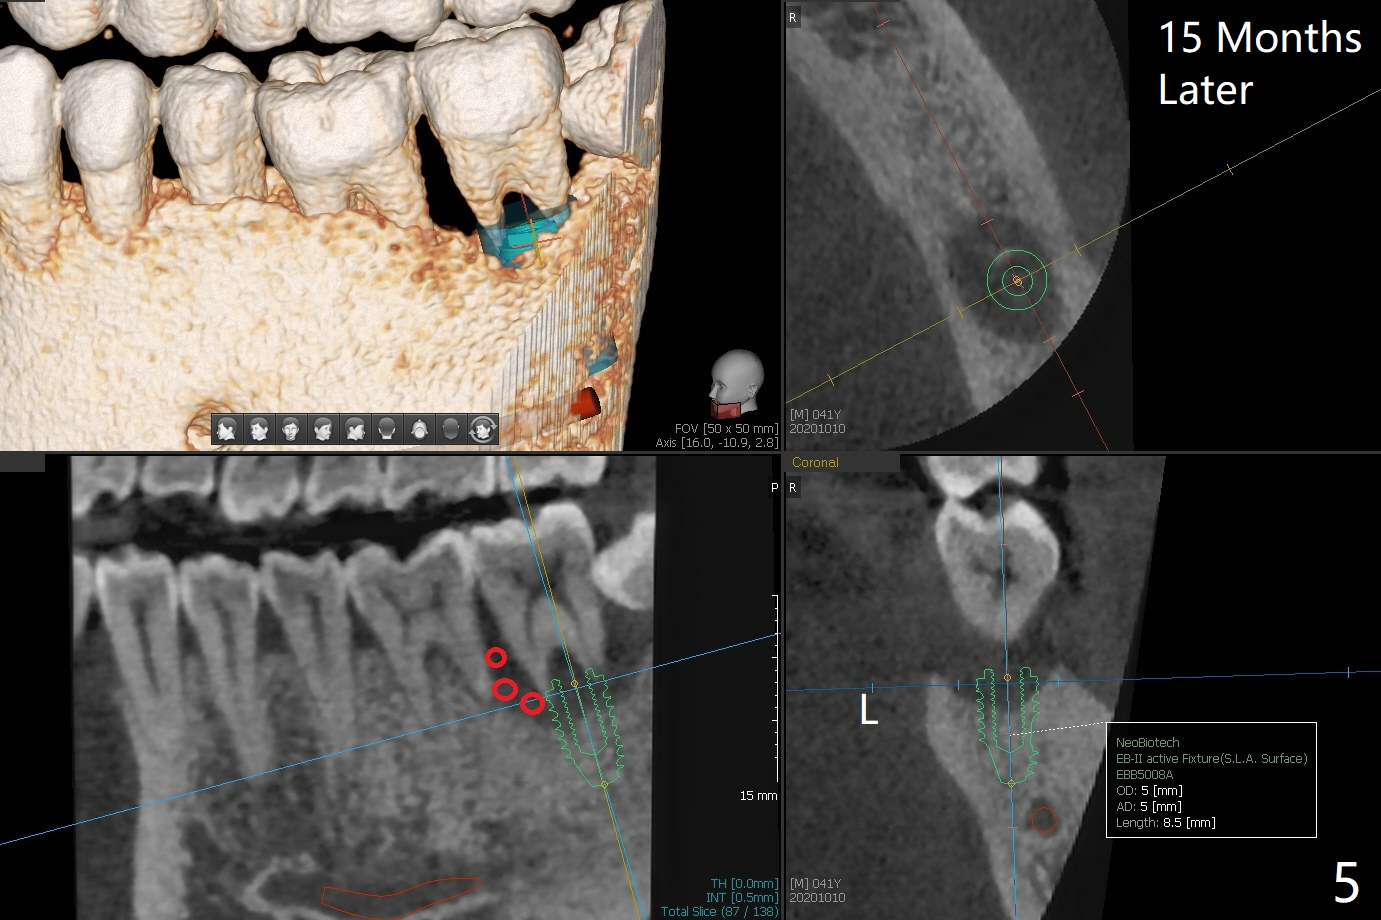

A 40-year-old man (smoker, 1ppd) is concerned about #31 mobility (Fig.1). Gross debridement is finished in his 1st appointment, while impression is taken for guide in his 2nd one. SRP has been scheduled for lower right quadrant with #31 extraction and immediate implant (Fig.2). The tooth #17 extraction will be postponed. The extraction may lead to mobility of the tooth #18, although SRP for the other 3 quadrant will be scheduled 1 week post #31 surgery. Smoke reduction is encouraged. When the crown is delivered at #31 one year later, the tooth #18 is loose (Fig.3) with lingual fistula. Since bone loss is more severe lingual (L *), a 5x10 mm immediate implant will be placed buccal (Fig.4). The tooth #17 will be kept as a distal stop for guide and extracted after #18 implant placement. Bone loss at #18 is more severe with mobility 15 months later; a shorter implant will be placed (Fig.5). After local scaling & root planing of the distal surface of #19 and application of Endogain, place sticky bone (red circle). Insert Collagen or Osteogen Plug in the #17 sockets.